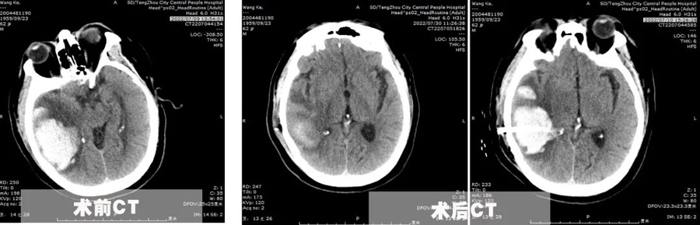

患者王先生,62歲,體重200余斤,糖尿病、冠心病、腦梗塞病史3年余,長期口服二甲雙胍、阿司匹林、瑞舒伐他汀等藥物,病情控制一般。7月8日,患者突發(fā)頭痛頭暈,出現(xiàn)一側(cè)肢體偏癱、意識障礙,急診行顱腦CT提示枕頂葉大面積腦出血,血腫量超過50ml,有手術(shù)指征。

為了在最恰當(dāng)?shù)氖中g(shù)時機(jī)及時完成手術(shù),7月10日,李永濤主任放棄在家休息的時間,帶領(lǐng)陳凡宇主治醫(yī)師,在局麻下為患者完成顱骨鉆孔腦出血引流術(shù)。術(shù)中僅在切口線注入5ml利多卡因,然后顱骨鉆孔形成直徑約1cm骨孔,切開硬腦膜后精準(zhǔn)置入直徑約5mm的硅膠引流管于血腫腔,術(shù)后復(fù)查CT并引流管內(nèi)注入尿激酶促進(jìn)血腫引流。經(jīng)過3天的引流,血腫基本排除,腦壓下降,癥狀改善。同時盡早給予患者床旁肢體功能康復(fù),并積極調(diào)整患者血糖、血壓、及心臟功能,給予患者精神鼓勵和心理輔導(dǎo)?;颊叱鲈旱臅r候已經(jīng)能夠獨(dú)立行走,生活自理。